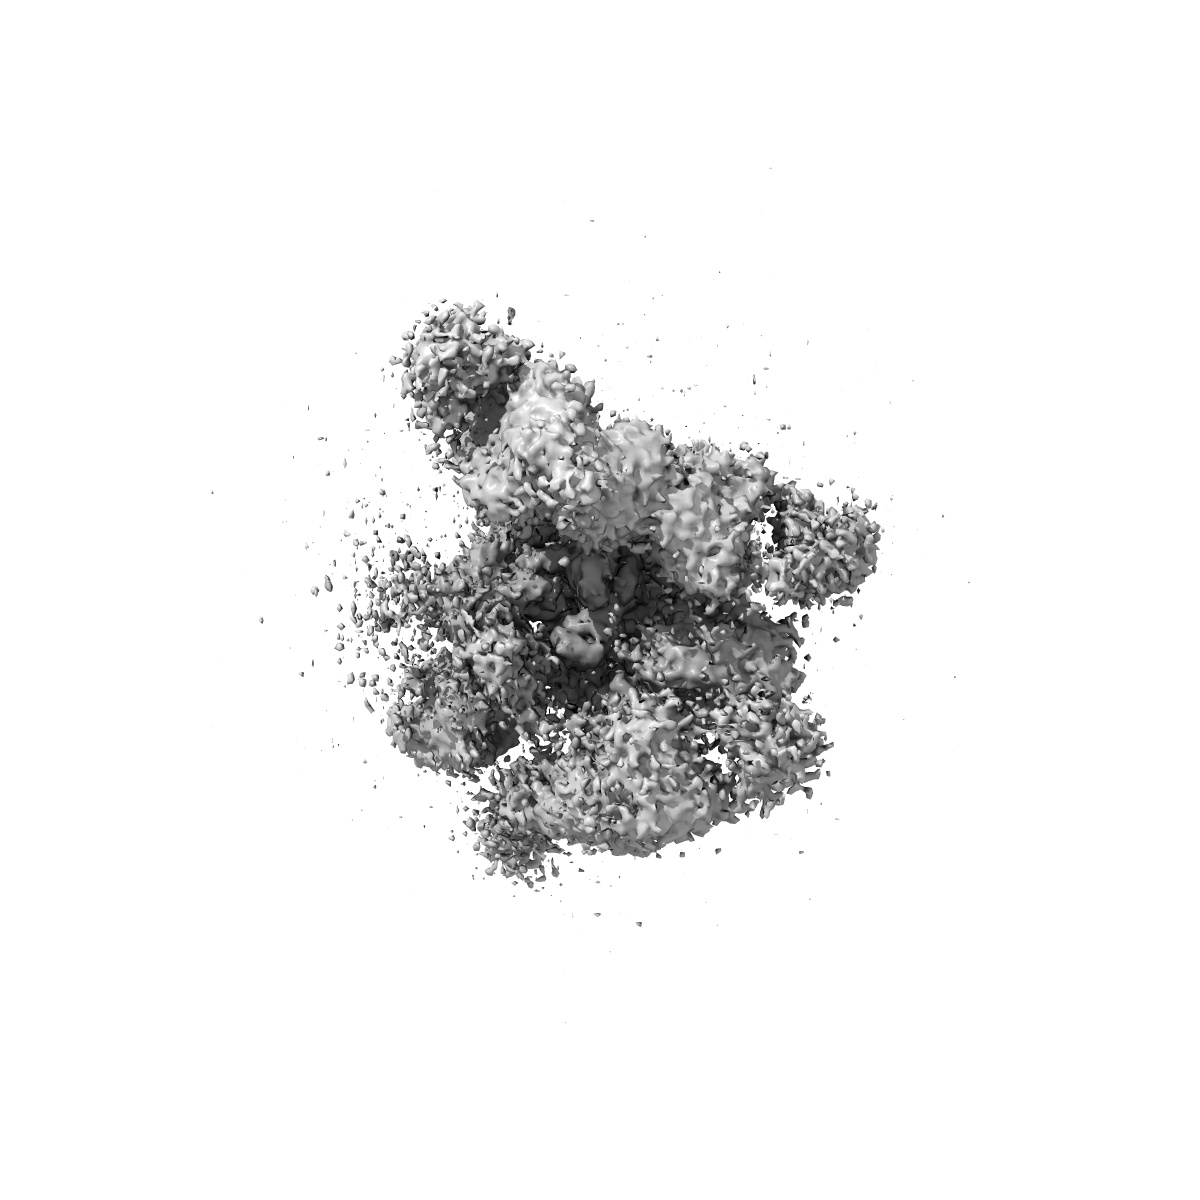

SARS-CoV-2 spike trimer (6P) in complex with two H18 and two R1-32 Fabs

Single-particle3.96 Å

Sample: SARS-CoV-2 spike trimer (6P) in complex with two H18 and two R1-32 Fabs